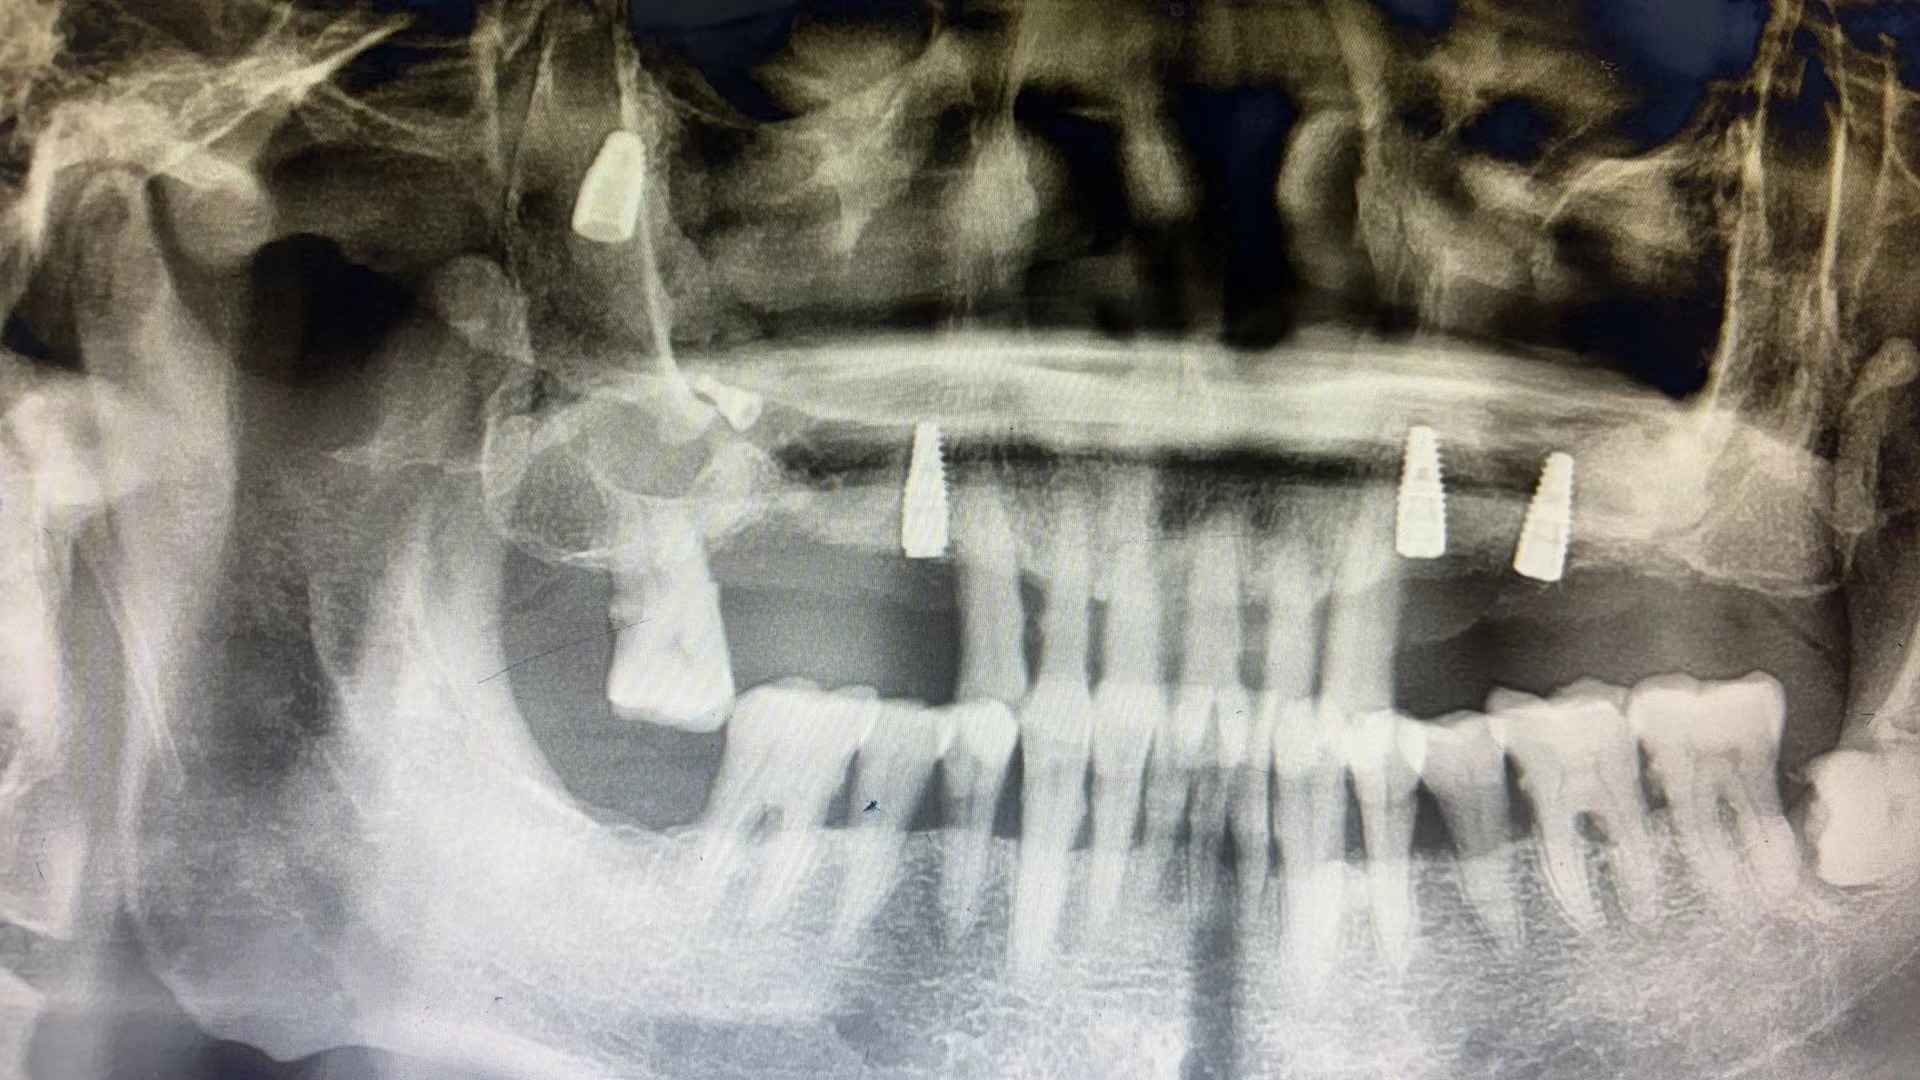

种植体掉入上颌窦了

种植体并发症

严重的种植并发症一例

种植牙并发症之一,植体掉入上颌窦